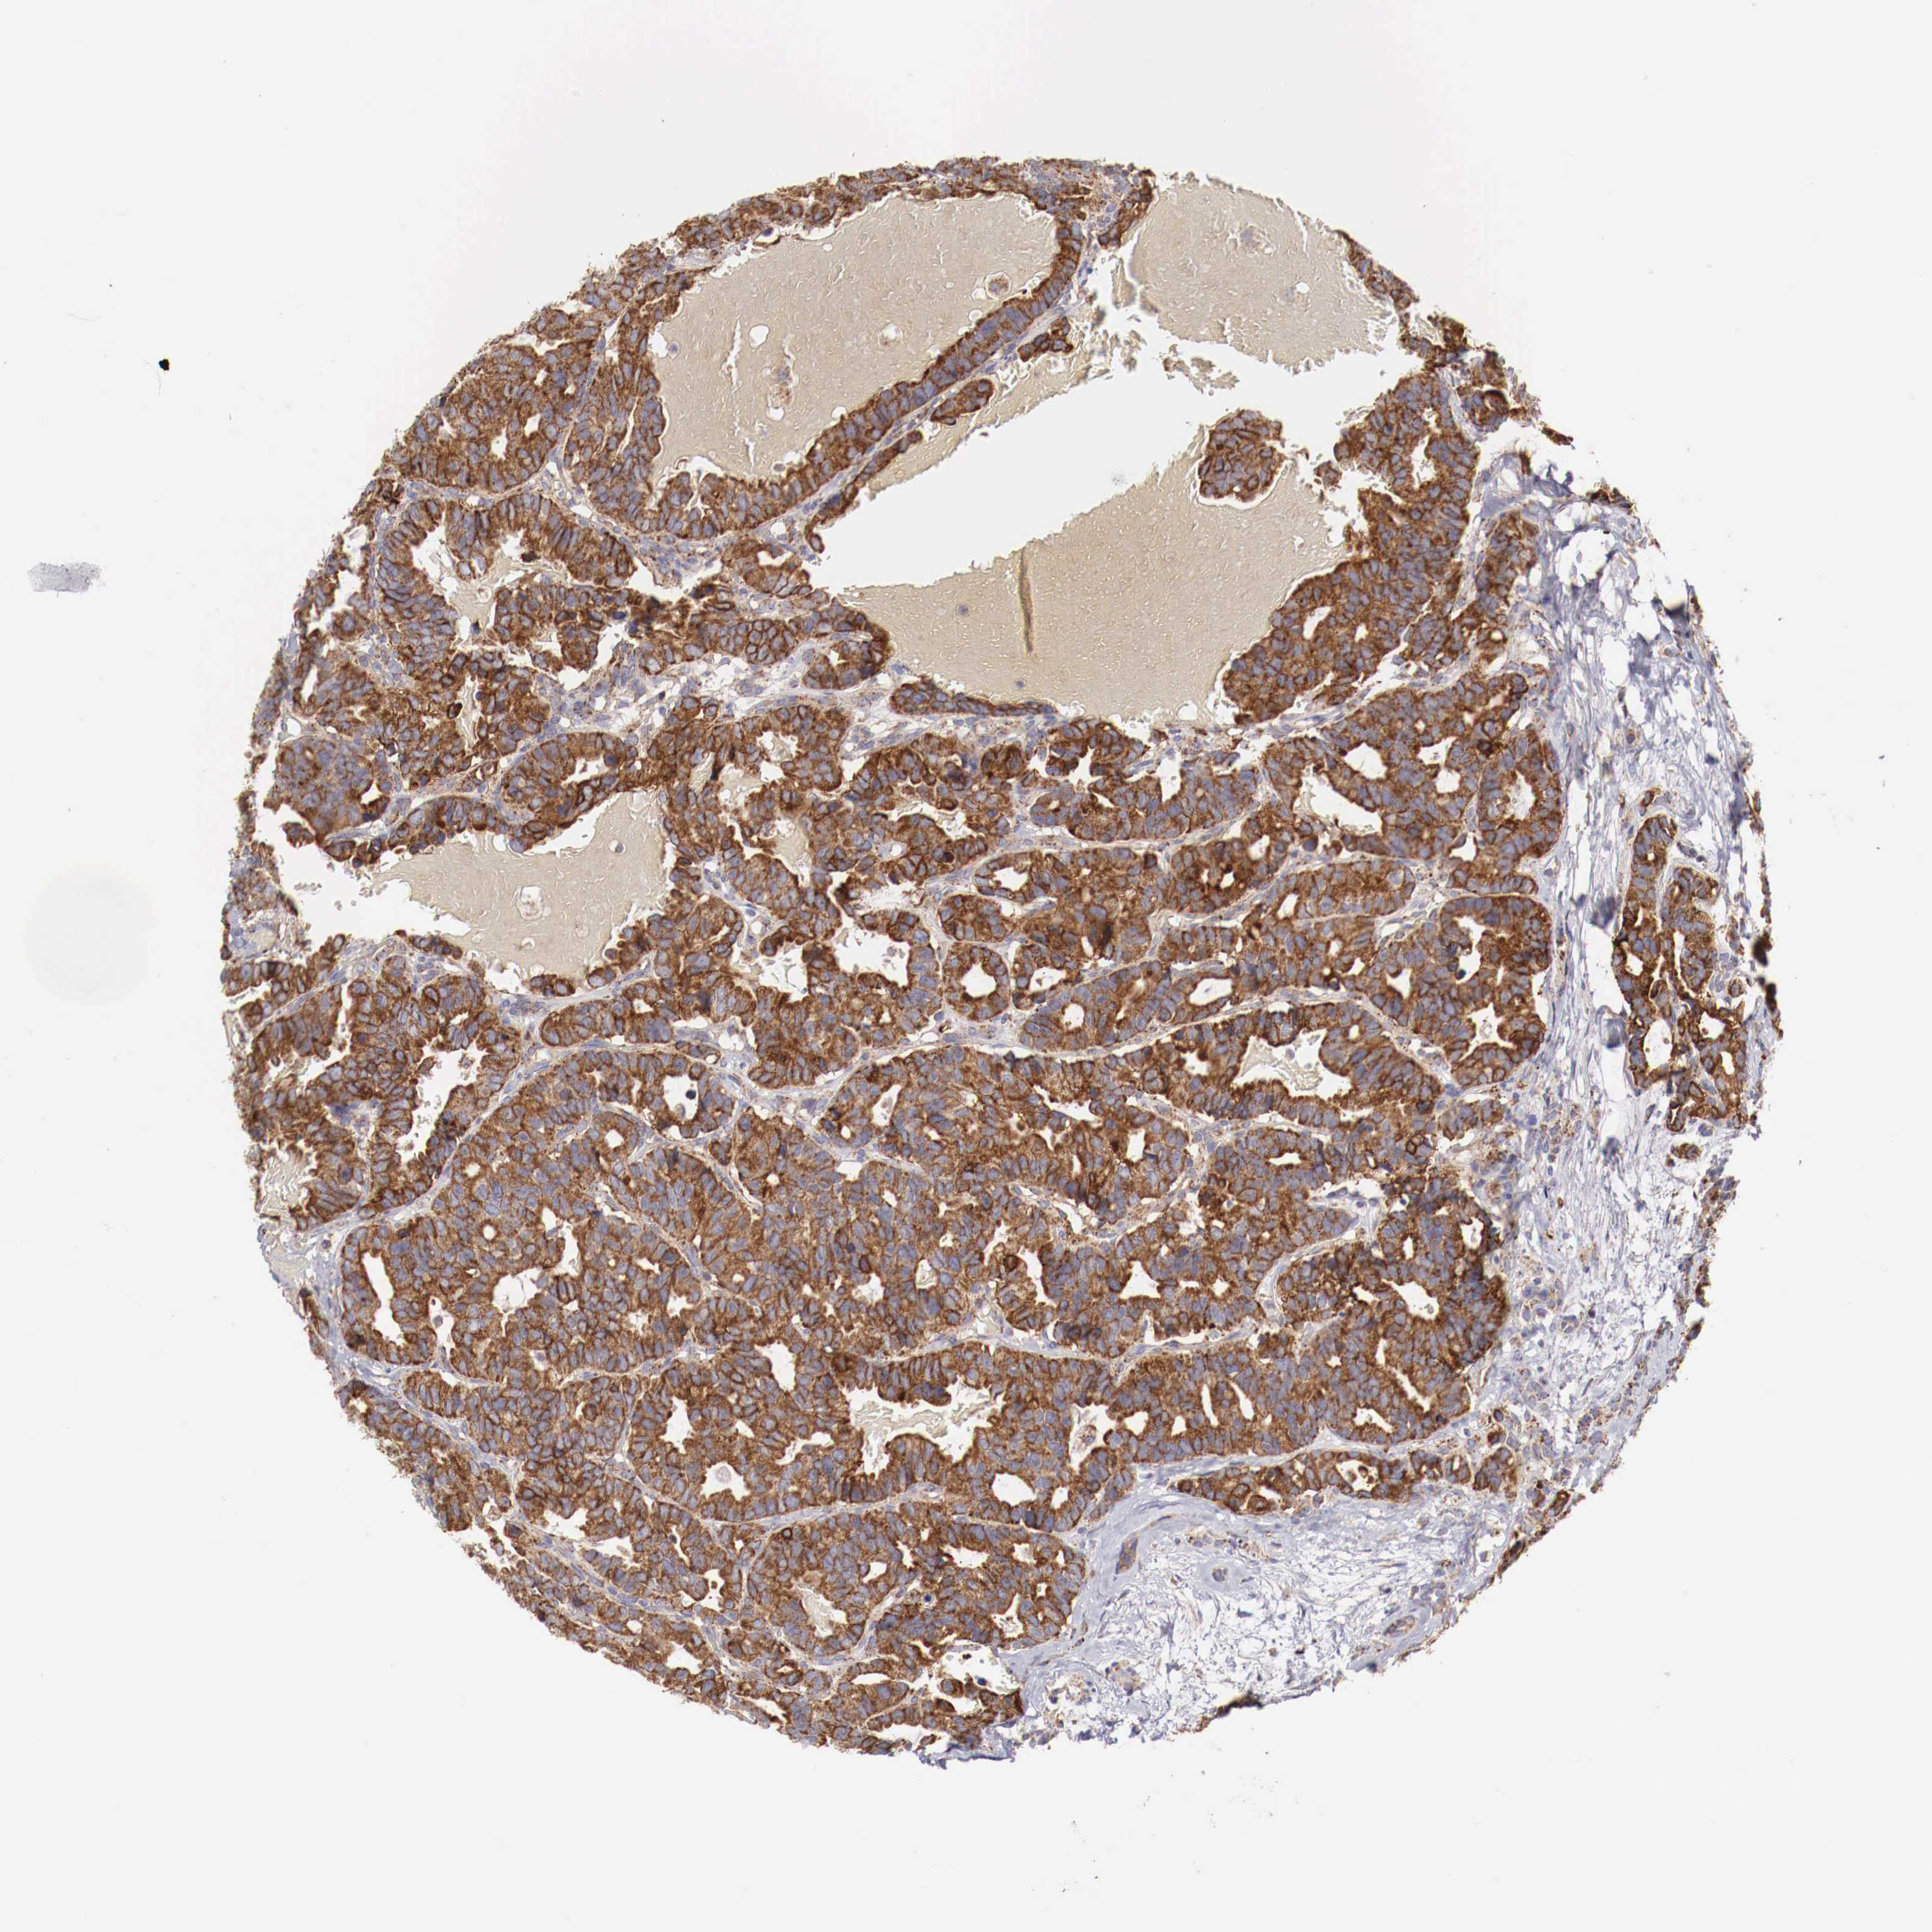

BRCA TCGA BRCA VALIDATION PROTEIN EXPRESSION